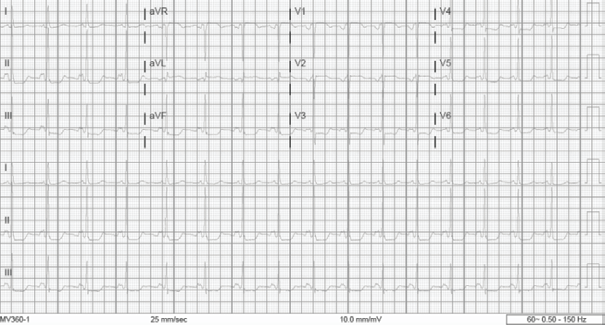

FIGURE 1: Initial EKG were notable for a leukocytosis of 23.19 k/uL, lipase of 87 U/L and an initial negative troponin of 3 ng/L HEART score of 1. The patient denied any chest pain or shortness of breath. A repeat ECG completed shortly after epigastric pain was controlled showed dynamic STE in aVL, V1 and aVR with diffuse ST depressions (see Figure 2). (Click to enlarge.)

During the initial work-up, her ECG revealed STE measuring approximately 1 mm in V1, V2. There was also STE approximately 1 mm in I and aVL with diffuse ST depressions in the inferior leads, V3-V6 and aVR (see Figure 1).